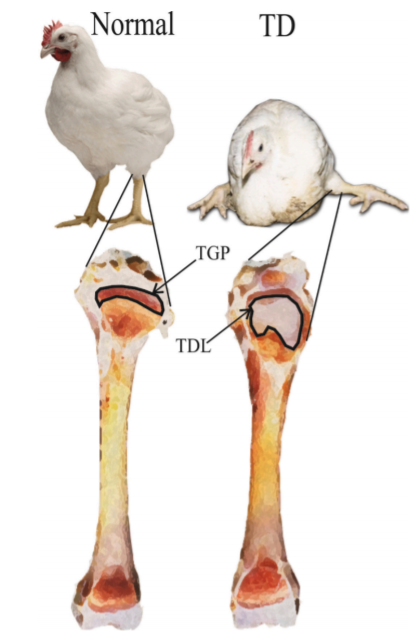

É possível separar as aves afetadas por problemas locomotores em diferentes categorias de acordo com a sua idade e/ou sistema produtivo. Frangos de corte são aves selecionadas para o rápido desenvolvimento, e comumente são afetadas por distúrbios do crescimento ósseo. São desordens que ocorrem durante o crescimento, sendo de natureza do próprio desenvolvimento da ave – ou metabólica, resultado em patologias de crescimento ou anormalidade da modelagem óssea (Fernandes, 2012). Os principais problemas nestas aves de rápido desenvolvimento são a deformidade angular e torcial, a discondroplasia, o raquitismo, a osteocondrose e a condrodistrofia.